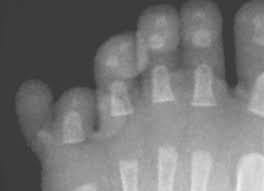

People Born With Extra Fingers Or Toes Requires Extra Brain S Resources Tech Explorist

People Born With Extra Fingers Or Toes Requires Extra Brain S Resources Tech Explorist from cdn.techexplorist.com